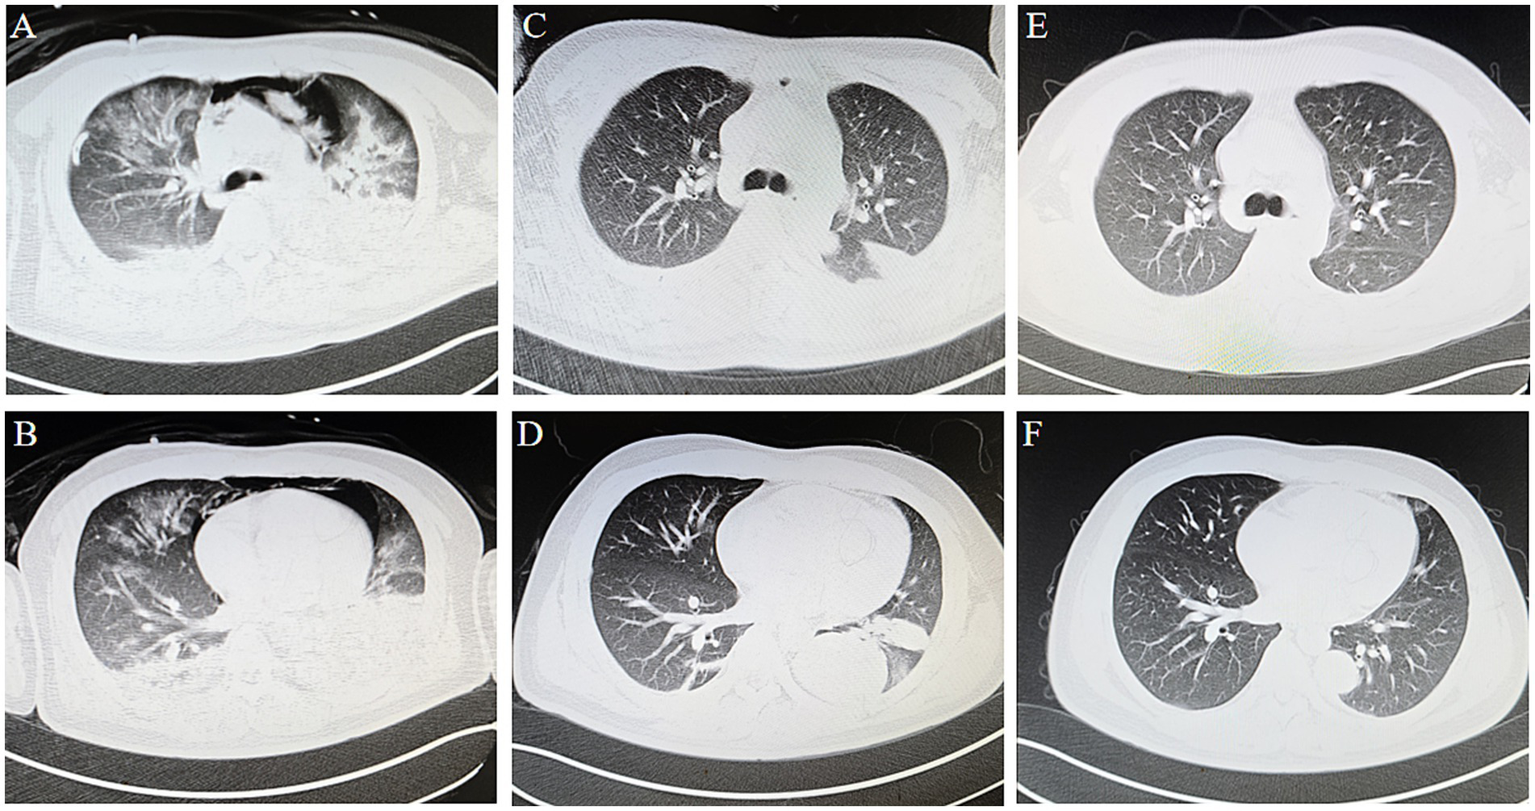

As the patient’s oxygenation improved, ECMO parameters were progressively weaned while ventilator support was concomitantly increased. By 72 h post-ECMO initiation, serial chest radiographs demonstrated marked resolution of the right pneumothorax (Figure 1B). Thoracic CT revealed persistent diffuse bilateral pulmonary edema with extensive ground-glass opacities and consolidative patches (Figures 4A,B). Concurrently, laboratory indices showed progressive normalization of hepatic and renal function (Table 1). Subsequently, the patient was successfully weaned from ECMO.

Figure 4

Thoracic CT. (A,B) At 72 h of ECMO, CT demonstrating bilateral pulmonary edema with extensive ground-glass opacities, patchy consolidations and pneumomediastinum. (C,D) Thoracic imaging demonstrated complete resolution of pulmonary edema, with residual consolidative opacities persisting in bilateral lower lobes. (E,F) The 3-month follow-up showed that the patchy shadows were significantly reduced, and had basically recovered.

By ICU day 23, follow-up thoracic CT demonstrated substantial pulmonary recovery with residual left lower lobe consolidative opacities (Figures 4C,D), paralleled by normalization of hepatic and renal function biomarkers (Table 1). These improvements prompted ICU discharge to general ward care. No ECMO-or ventilator-associated complications occurred during hospitalization.

At the 3-month outpatient follow-up, repeat imaging revealed near-complete resolution of consolidative lesions (Figures 4E,F). The patient reported full resumption of premorbid activities (6-min walk distance: 420 meters) without exertional dyspnea (mMRC grade 0). At the 9-month follow-up, the patient reported that tests at other hospitals showed that the indicators had returned to normal.